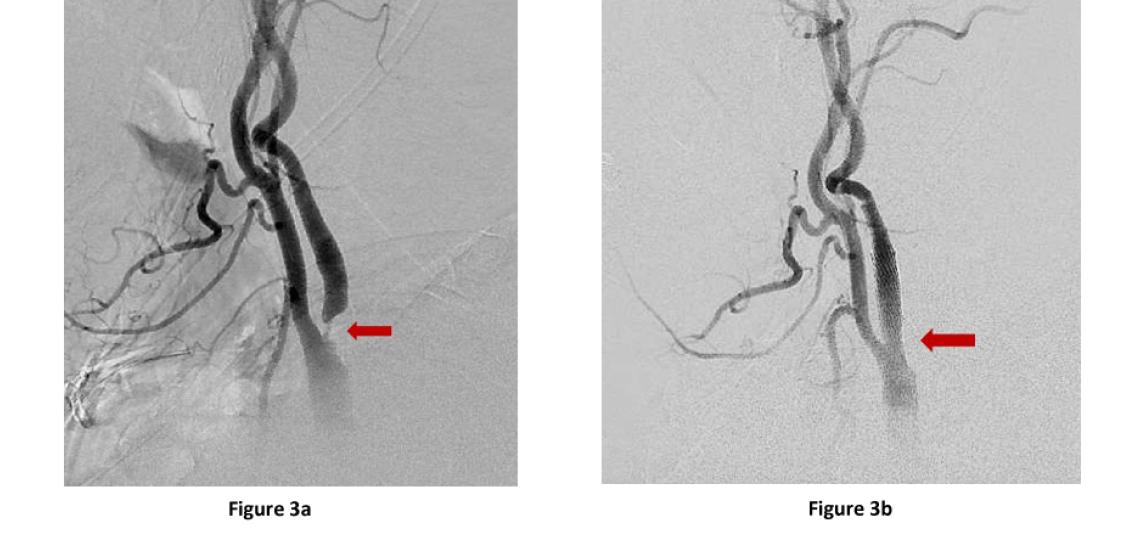

Carotid Stenting - Alternatively, for select patients, carotid angioplasty and stenting, may be recommended. This procedure involves placing a self-expanding stent in the artery at the site of the narrowing and the stent expands holding the artery open (Figure 3), thereby, reducing the risk of future strokes.

Figure 3a: Neck angiogram lateral (side) view of the left carotid artery. There is severe stenosis or narrowing of the internal carotid artery (red arrow) at its origin. Figure 3b: Lateral view of the same patient after placement of a carotid stent showing full re-opening of the stenosis (red arrow).